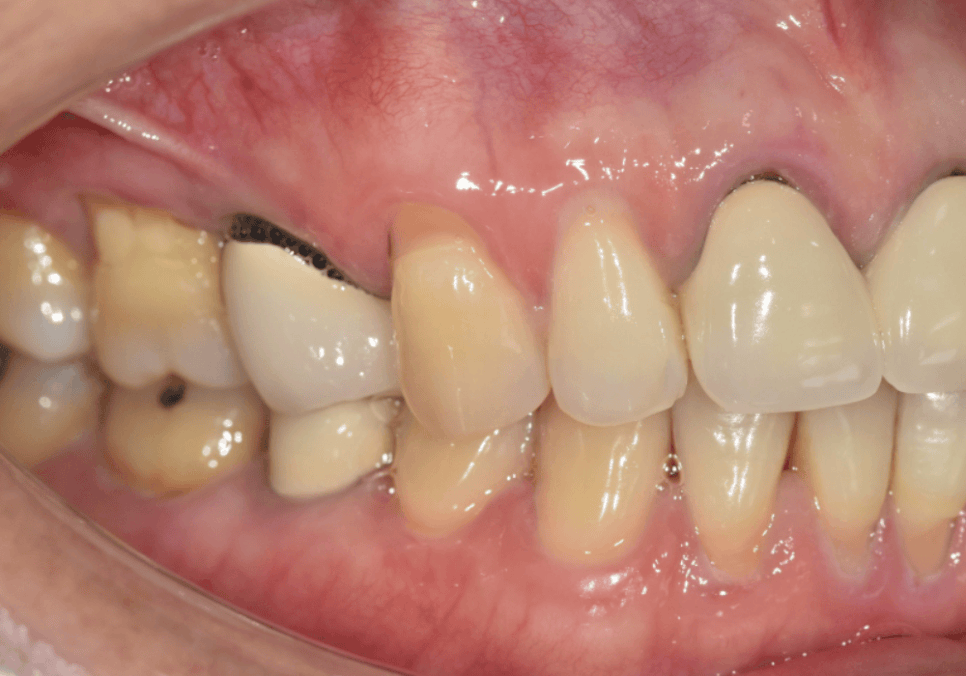

PFM 도자기 계열 보철물은

안쪽에 금속 구조물이 들어가 있습니다.

처음엔 잇몸으로 가려져 있지만

시간이 지나면서

잇몸 까매짐 원인,증상,치료 방법

잇몸이 조금씩 내려가면

안쪽 금속 테두리가 비쳐 보이면서

검게 보일 수 있어요.

이 경우엔 치아 자체는 건강하다면

단순히 심미적인 문제이기 때문에

안에 금속이 없는 지르코니아 크라운이나

올세라믹 크라운으로 교체하면 해결됩니다.